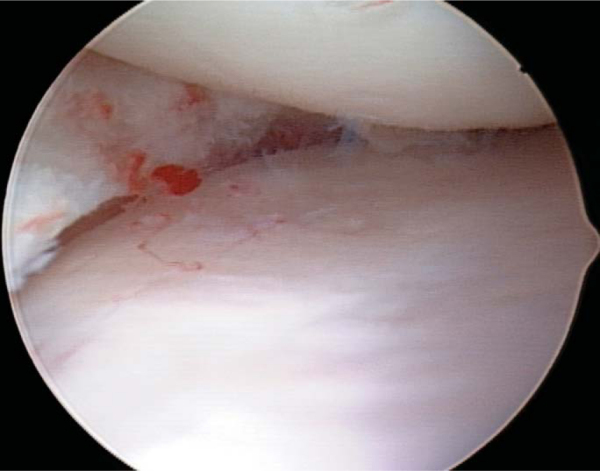

The initial steps for medial and lateral meniscus transplantation are similar. The remaining meniscus is débrided to a stable, 1- to 2-mm peripheral rim until punctate bleeding occurs (

Fig. 47-4

). The most anterior aspect of the meniscus can be excised under direct visualization by use of a No. 11 scalpel blade placed through the ipsilateral portal followed by the use of an aggressive arthroscopic shaver. The anterior and posterior horn insertion sites should be maintained because they are helpful markers during slot preparation. A limited notchplasty along the most inferior and posterior aspect of the ipsilateral femoral condyle allows improved visualization of the posterior horn and facilitates graft passage.